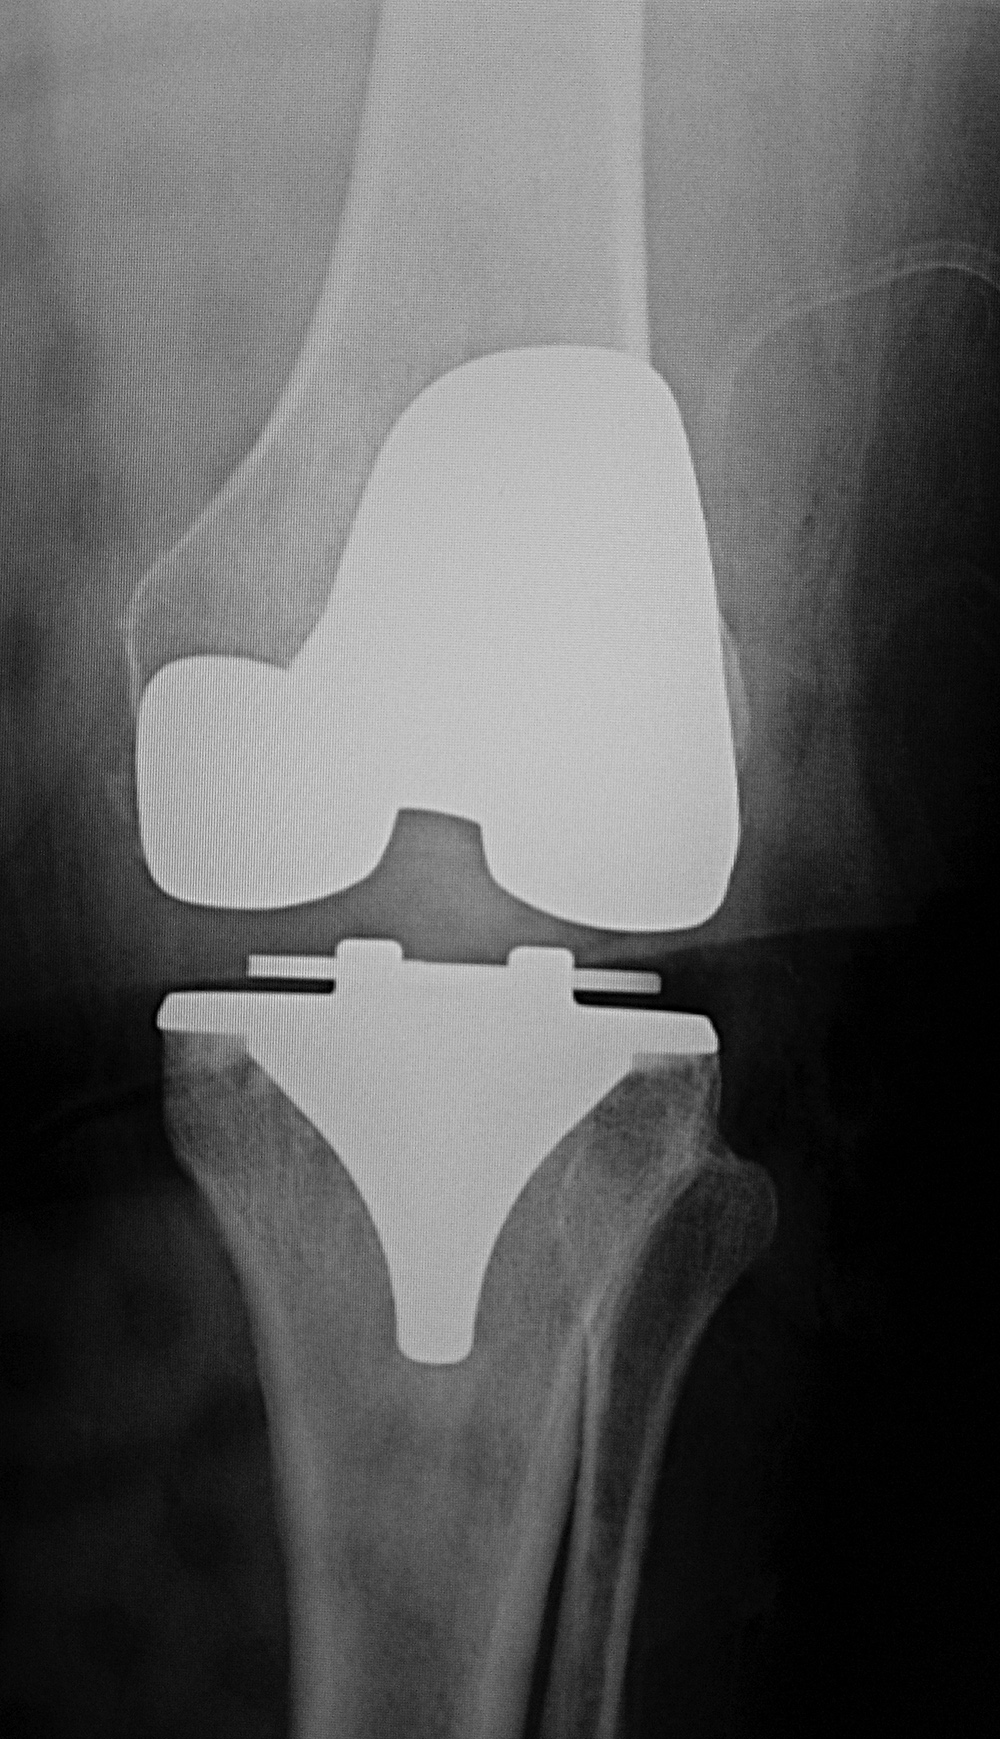

Subtle failure of total knee arthroplasty (TKA) |

A noncemented total knee arthroplasty is present with a metal backed patellar component. There is also a polyethylene locking clip which locks the tibial polyethylene into the tibial base plate. The anterior cortex of the femur is notched and eroded (top arrow). There is also subtle subsidence of the tibial component (bottom arrow). From Benjamin, 1994 |